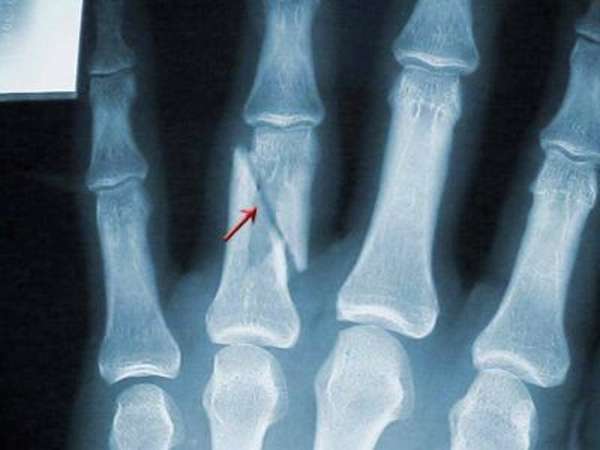

Фаланги

Чаще всего, от перелома страдают отдельные фаланги пальца руки. Различают переломы:

- проксимальной фаланги,

- средней фаланги,

- дистальной фаланги (первой).

Травма основной фаланги встречается чаще остальных

Перелом ногтевой фаланги часто происходит из-за неосторожности при работе с молотком или другими инструментами. Для травмы верхней фаланги характерно массивное раздробление кости и повреждение кожи, которое может привести к инфицированию. Интересно почитать перелом кисти руки

Переломы делят на две группы в зависимости от того, как расположены отломки: со смещением, без смещения. Перелом пальца со смещением может быть с расхождением или захождением отломков.

По количеству осколков выделяют: безоскольчатые, одно-, двух- и многооскольчатые. По форме линии разлома различают поперечный, винтовой, косой, Т-образный, S-образный и другие виды повреждения. По месторасположению бывают околосуставные, внутрисуставные и внесуставные или переломы диафизарной части.